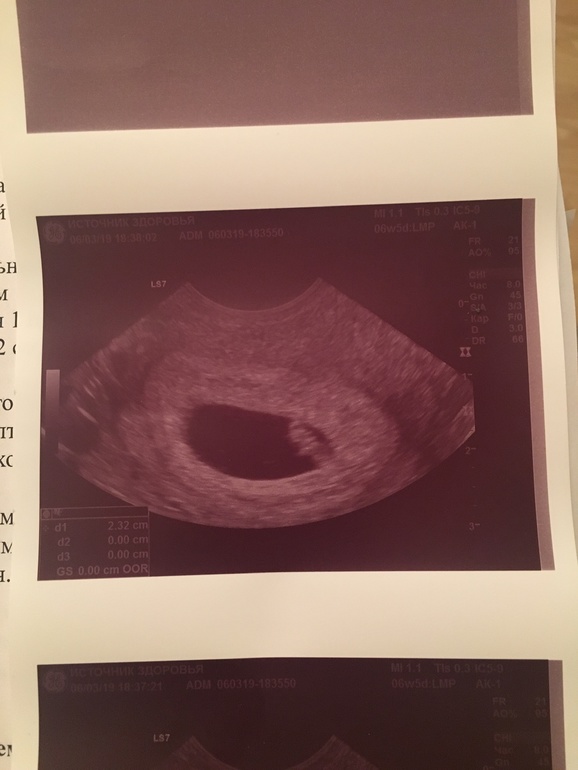

6 нед 4 дн

Результаты: УЗИ, КТГ, доплера, скринингаВчера были на узи, есть эмбрион, СБ+

Познакомились с нашим червячком))))

КТР 0,66 см

ПДР 25-26 октября